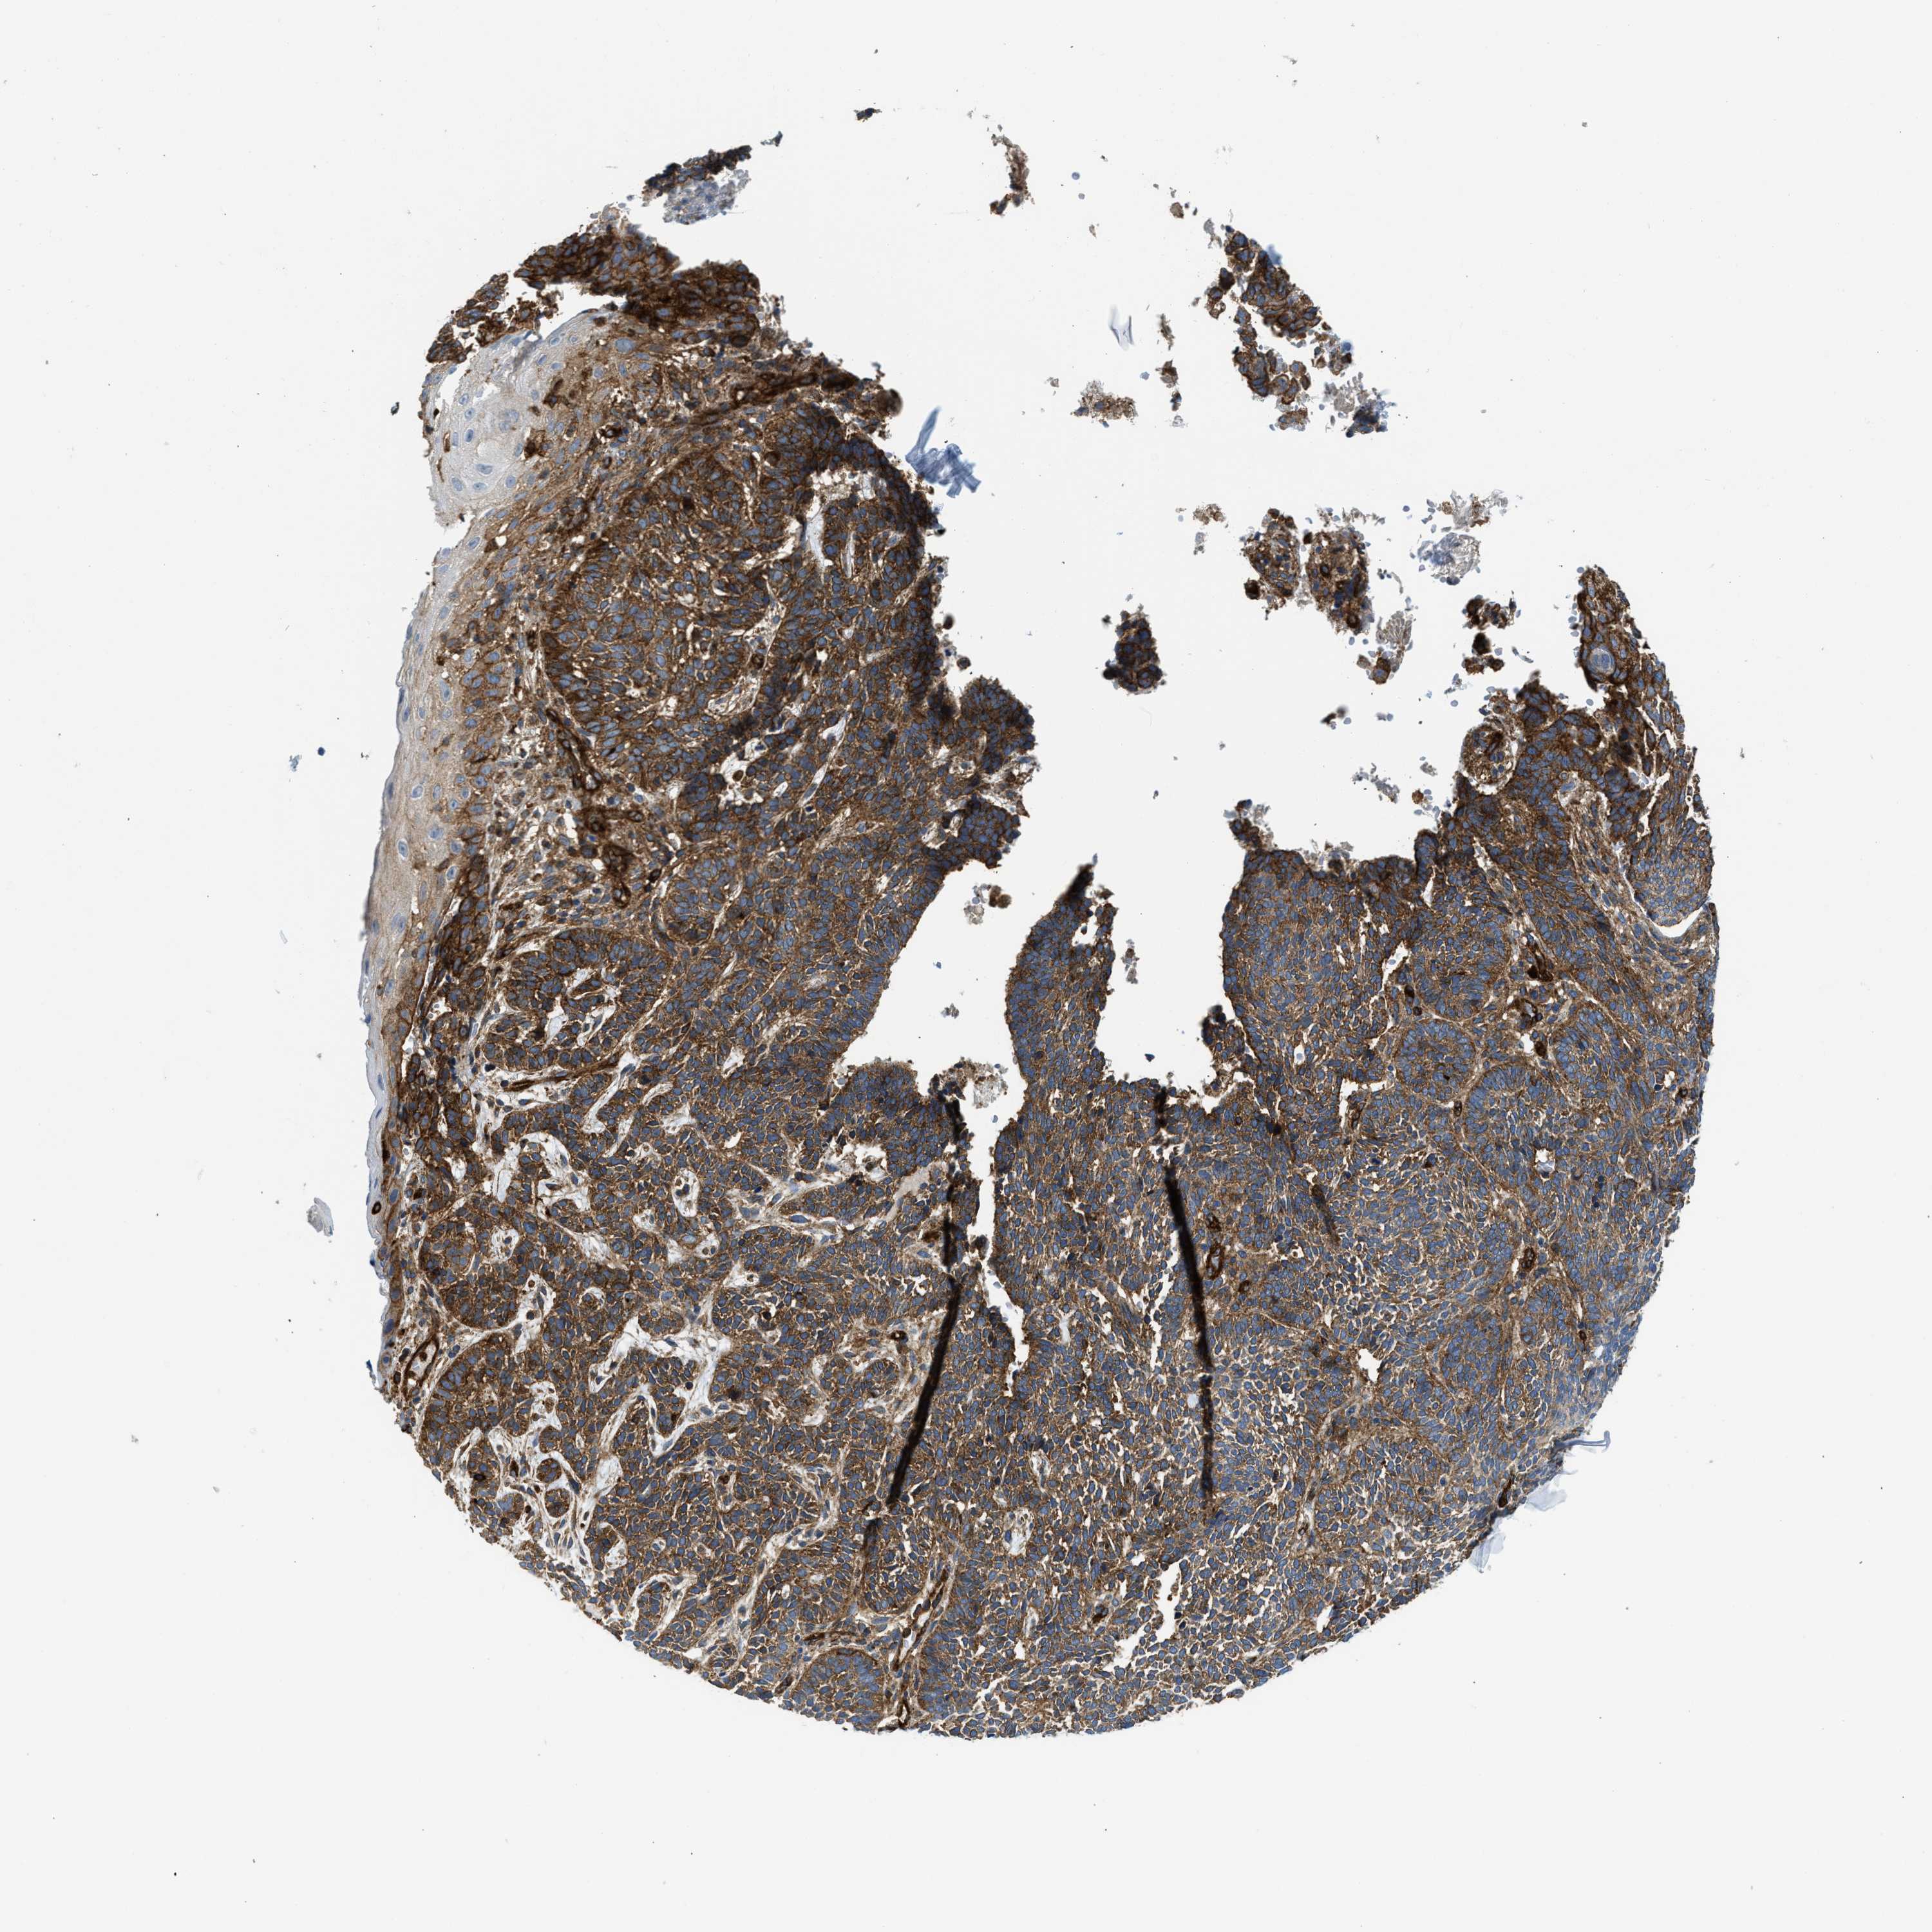

SKIN CANCER - Protein expressioni

A mouse-over function shows sample information and annotation data. Click on an image to view it in a full screen mode. Samples can be filtered based on level of antibody staining by selecting one or several of the following categories: high, medium, low and not detected. The assay and annotation is described here.

Antibody stainingi

Antibody staining in the annotated cell types in the current human tissue is reported as not detected, low, medium, or high, based on conventional immunohistochemistry profiling in selected tissues. This score is based on the combination of the staining intensity and fraction of stained cells.

Each image is clickable and will lead to virtual microscopy that enables deeper exploration of all samples and also displays staining intensity scores, fraction scores and subcellular localization as well as patient and tissue information for each sample.

Antibody HPA013606

Antibody HPA017964

Antibody CAB015334

Antibody CAB016402

Staining

High

Medium

Low

Not detected

Intensity

Strong

Moderate

Weak

Negative

Quantity

>75%

75%-25%

<25%

None

Location

Nuclear

Cytoplasmic/membranous

Cytoplasmic/membranous,nuclear

Squamous cell carcinoma in situ, NOS

Squamous cell carcinoma, NOS

Squamous cell carcinoma, metastatic, NOS

Basal cell carcinoma

Adnexal tumor, benign